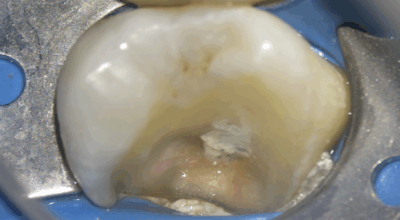

Clinical case

Full pulpotomy: 91.3% success rate